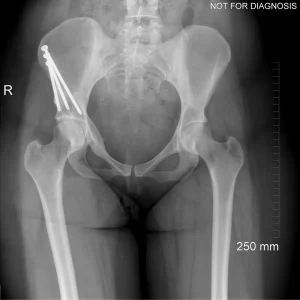

• Diagram 3: Hip After Periacetabular Osteotomy (PAO)

Diagram 3: Hip After Periacetabular Osteotomy (PAO)

• Acetabulum repositioned to improve femoral head coverage

• Load more evenly distributed across the joint

• Screws shown securing the acetabulum in its new position

These diagrams are commonly used in clinic to help patients visualize the problem and understand how PAO corrects hip mechanics. Dr Grammatopoulos will review your X-rays alongside these illustrations to explain your individual anatomy and surgical plan.